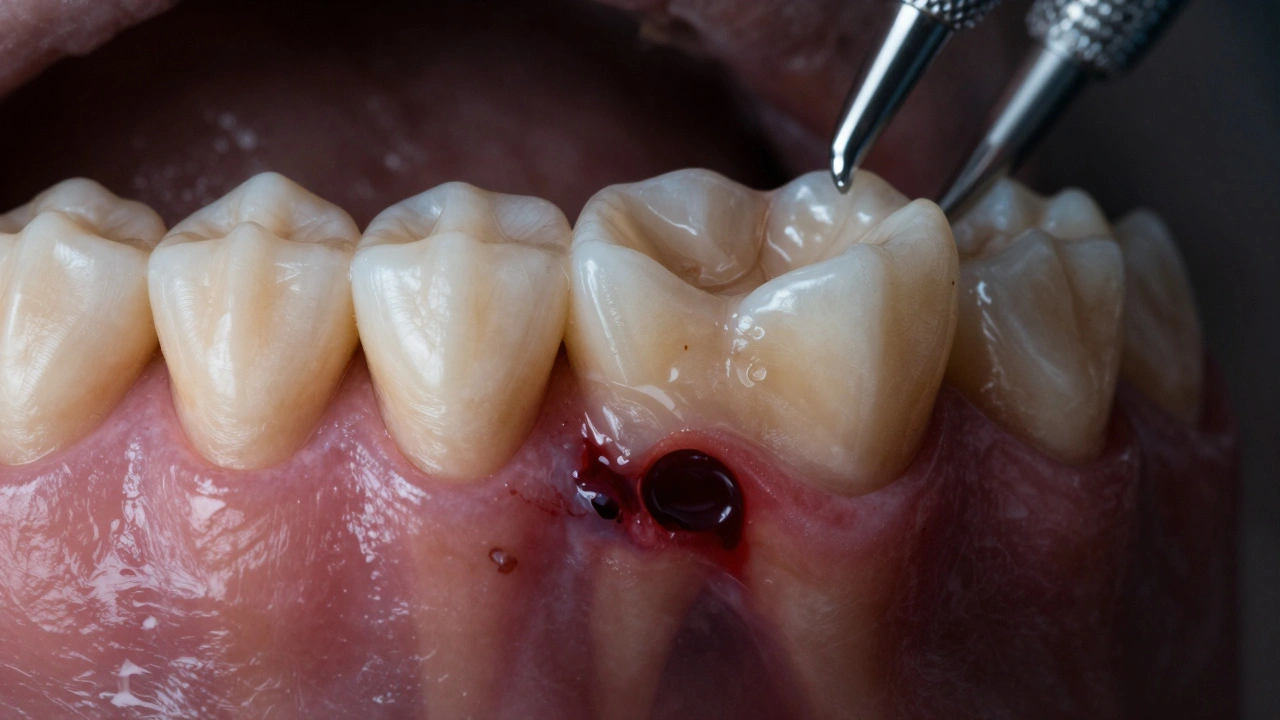

- Žlutý nebo hnědý výtok z dásně - pokud se vytvoří pustula (malý vřídek), může z něj vytékat hnis. To je jasný signál, že infekce je aktivní.

Zubní lékař provede rentgen a zjistí, zda je infekce v kořeni, v kosti nebo obou. Pokud je zub ještě zachránitelný, provede se reendodontie - znovu očistí kanálky a zub se znovu zapečetí. Pokud je kost příliš poškozená, zub se musí vyjmout.